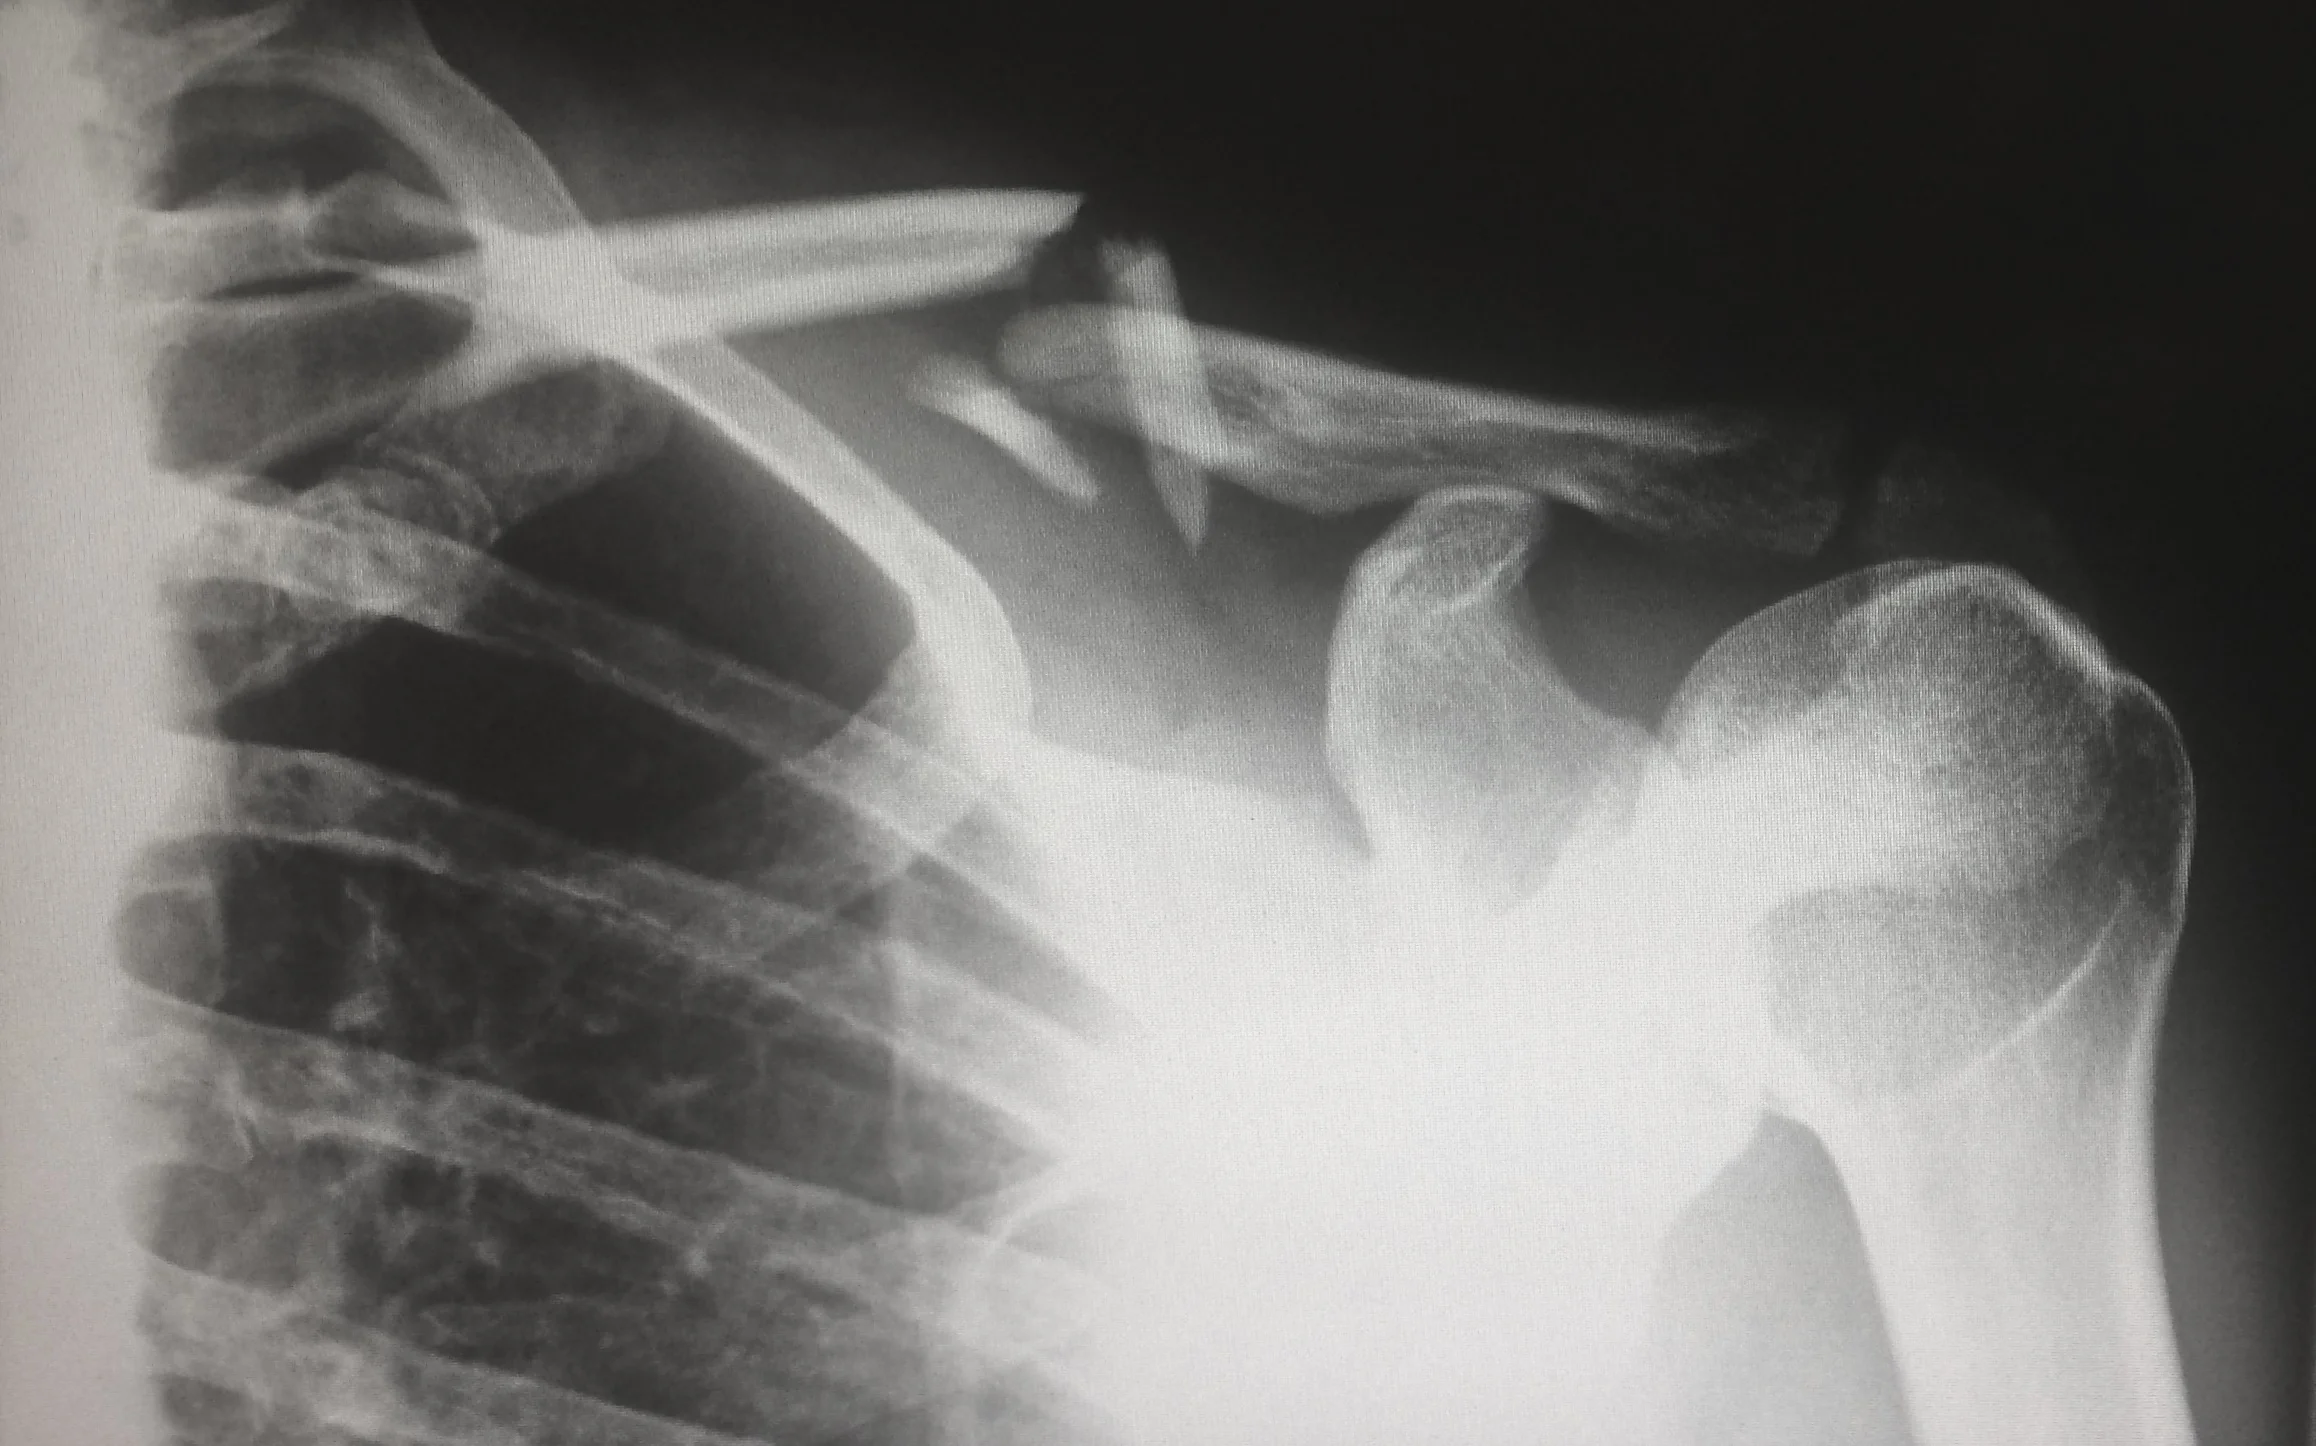

Two months earlier I crashed my bike and separated my shoulder while training for a triathlon. I was in a sling for nearly two weeks and had to have my fingernail stitched onto my finger so that it wouldn’t fall off! I was devastated. I started training for the Lake Placid half Ironman in January. I had little training since the crash and wanted to pull out of the race. Of course, I would have to forfeit my nearly $400 entry fee, my 6 months of training and diet, my sacrifice, my discipline, my personal goal I set for myself to start the year. I couldn’t run, I was afraid to ride and I definitely could not swim. Failure and depression tried to set in. How could it not when you feel useless…helpless? I couldn’t even get dressed without excruciating pain! Sleep was non-existent and training was done for.